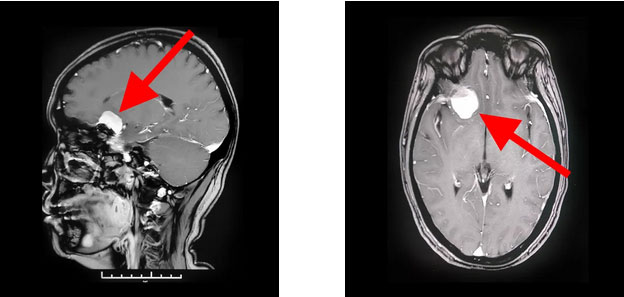

为寻求进一步治疗,经亲友推荐,胡女士慕名前来上海蓝十字脑科医院。入院后,行头颅磁共振增强扫描后确认,患者右侧颅底蝶骨嵴-鞍结节区实性占位,考虑为脑膜瘤且血供丰富;右侧大脑前动脉A1段与瘤灶贴近。

▲ 蝶骨嵴脑膜瘤周围多重要神经血管

通过蔡司显微镜(双荧光)下可见,患者蝶骨嵴内侧硬脑膜下有淡红色肿物,血供丰富。肿物大小约2.5cm*2.5cm*1.5cm,肿瘤与额叶底面脑组织粘连,并有较多血管沟通。沈教授聚精会神,抽丝剥茧地自蝶骨嵴位置基底部将肿物从硬脑膜分离。在镜下保护好视神经和颈内动脉、大脑中动脉、大脑前动脉等大血管,“蚂蚁搬家”般将只有“鸽子蛋”大小的肿物一点一点逐步切除。整台手术历时近5个小时,患者术中失血约100毫升,未进行输血,安返监护室后进一步观察。经病理检查,该肿瘤确诊为脑膜瘤。

▲ 术后影像显示,肿瘤已被切除